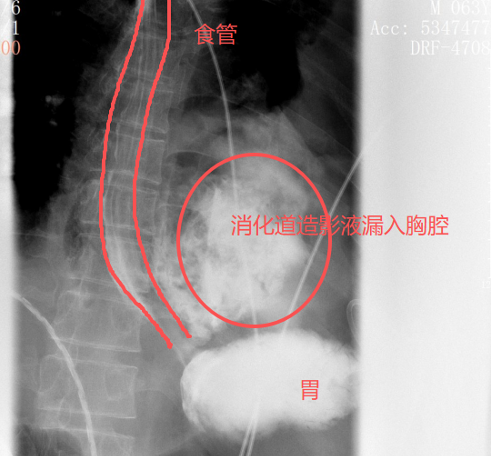

很快,口服钡餐的结果印证了他的判断:钡剂从食道下段的裂口处大量漏出,直接进入了左侧胸腔。

红圈区域是食物残渣、消化液破入食管